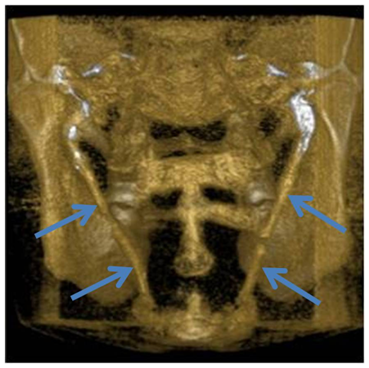

A 28-year-old man presented to the Department of oral and maxillofacial radiology of the Lebanese University complaining of dysphagia and vague throat discomfort that he had experienced continuously for less than a year. He also complained of a solid mass felt on palpation of the right and left tonsillar fossa and an occasional ‘‘shooting’’ pains to his both ears that lasted only a couple of minutes and then disappeared. His history was uneventful for any significant trauma. A panoramic radiograph (Figure 1) was obtained from an old lower third molar assessment where a calcification of both right and left stylohyoid ligament are observed. A CBCT exam (Figure 2) was conducted (Icat imaging sciences 120Kv, 24mA 0.4 voxel) with 3D reconstructions (Figure 3) which showed an elongated ossified styloid process on both sides, the thick calcified process extended from the stylomastoid foramen to the hyoid bone.

Figure 1 Panoramic view showing calcifications on both sides.